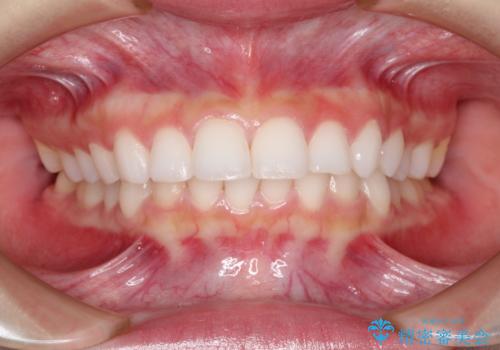

出っ歯の矯正治療 歯を抜かずにインビザラインで

- インビザラインで出っ歯を治したいとの希望がありました。

上顎の歯を全体的に後方に移動させて前歯を引っ込める計画としました。

インビザラインで目立たずに、痛みも少なく矯正治療を終えることができ満足していただけました。